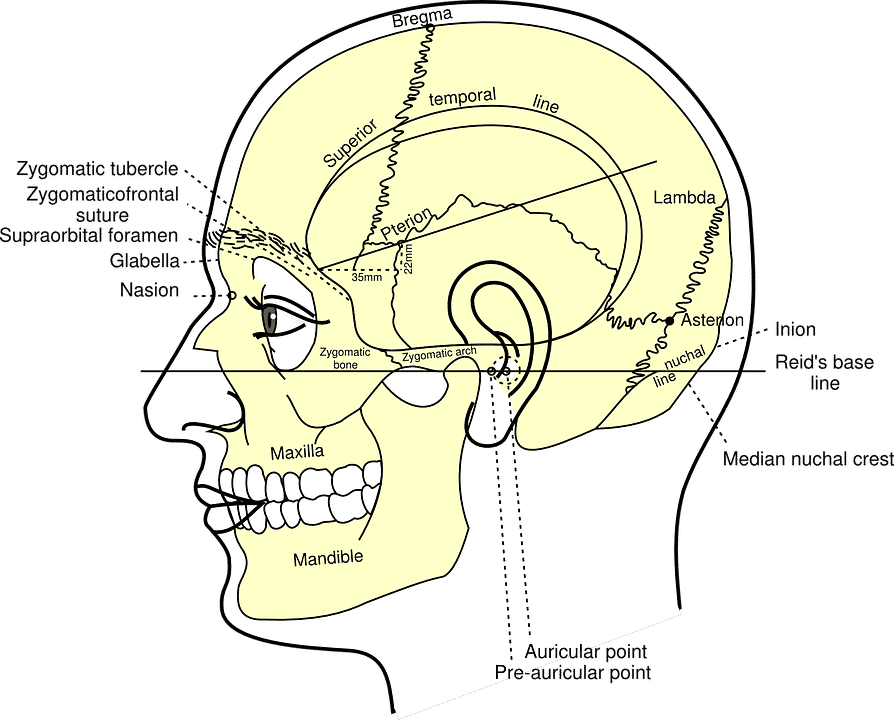

Generalmente decimos: “tengo dolor de cabeza”, queriendo decir que el dolor esta en la extremidad cefálica el cuerpo, pero, ¿qué nos está doliendo en realidad?

El cuero cabelludo, como parte de la piel, tiene una alta sensibilidad dolorosa, por tanto cualquier herida lo percibimos como dolor.

El periostio, que es una membrana fuerte y resistente que recubre los huesos del cráneo, es también sensible al dolor. El hueso en sí no lo es.

Por dentro del cráneo, el sistema nervioso estará cubierto por tres membranas:

- La duramadre que está pegada al hueso

- La aracnoides, de estructura la casa y por la que transcurre los pasos que entran y salen de la sustancia nerviosa

- La piamadre, delgada membrana que cubre la masa encefálica

Las tres son sensibles tanto por procesos inflamatorios (como la meningitis) como por la tracción o aumento del volumen de la masa encefálica (por un tumor, edema, hidrocefalia,…)

El cerebro, cerebelo, bulbo raquideo, etcétera, es decir, toda la sustancia nerviosa, es totalmente insensible, como la mayor parte de los organos internos del organismo (como el hígado, corazón,…)

Por último, los vasos arteriales venosos son sumamente sensibles a la tracción y distensión, siendo estos los motivos más frecuentes del dolor de cabeza, junto con el que provoca las contracturas de los músculos del cuello y las alteraciones reumaticas de las múltiples articulaciones en la columna vertebral.